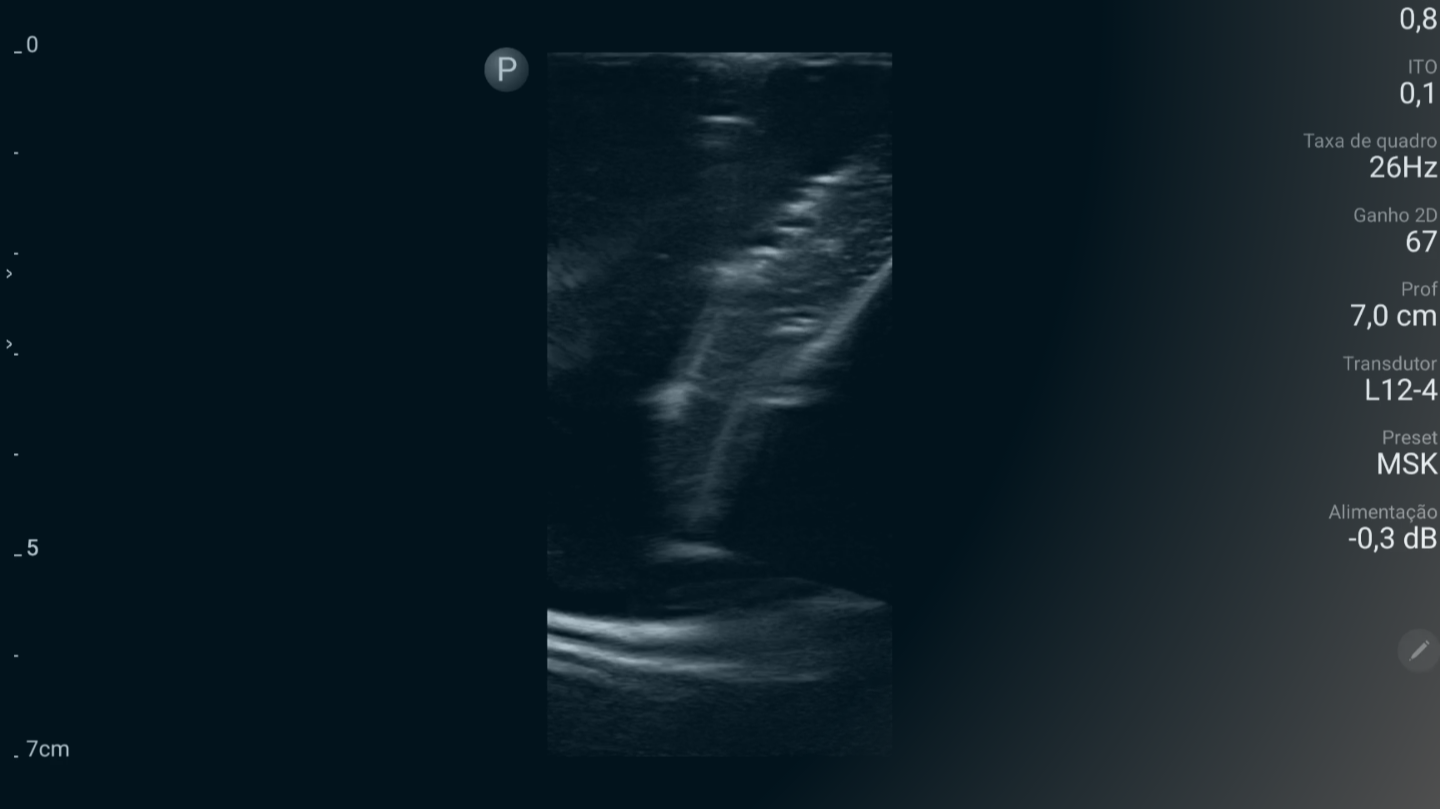

Domine a avaliação da congestão venosa sistêmica para guiar a terapia hídrica e otimizar o manejo de pacientes com insuficiência cardíaca e renal.

Entenda como a ultrassonografia pulmonar avançada orienta a infusão de fluidos e o manejo da insuficiência respiratória aguda.

Aprofunde-se na avaliação da função diastólica do coração para identificar disfunções cardíacas complexas.

Domine a técnica precisa para drenagem de derrames pericárdicos, minimizando riscos e aumentando a segurança do paciente.

Aperfeiçoe a inserção de cateteres centrais e outros acessos vasculares em situações desafiadoras.

Aprenda a guiar com ultrassom a drenagem de coleções pleurais e abdominais, garantindo posicionamento ideal e evitando complicações.